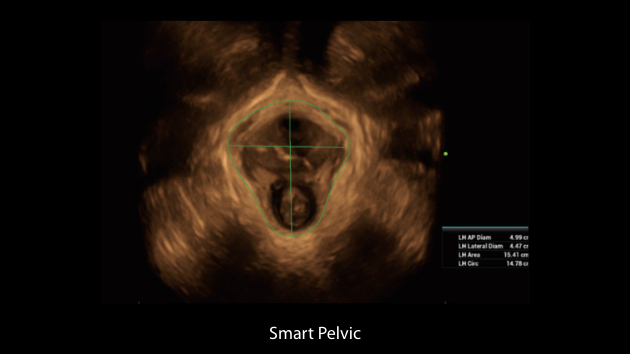

De Nuewa I9, speciaal ontworpen voor vrouwen en neonatale gezondheidszorg, biedt een innovatieve ervaring van binnenuit. Deze innovaties zijn ontwikkeld op basis van diepgaande inzichten in complexe klinische scenario's en bieden nauwkeurige en tijdige antwoorden, evenals een uitstekende effici?ntie en opmerkelijke gebruikerservaring.